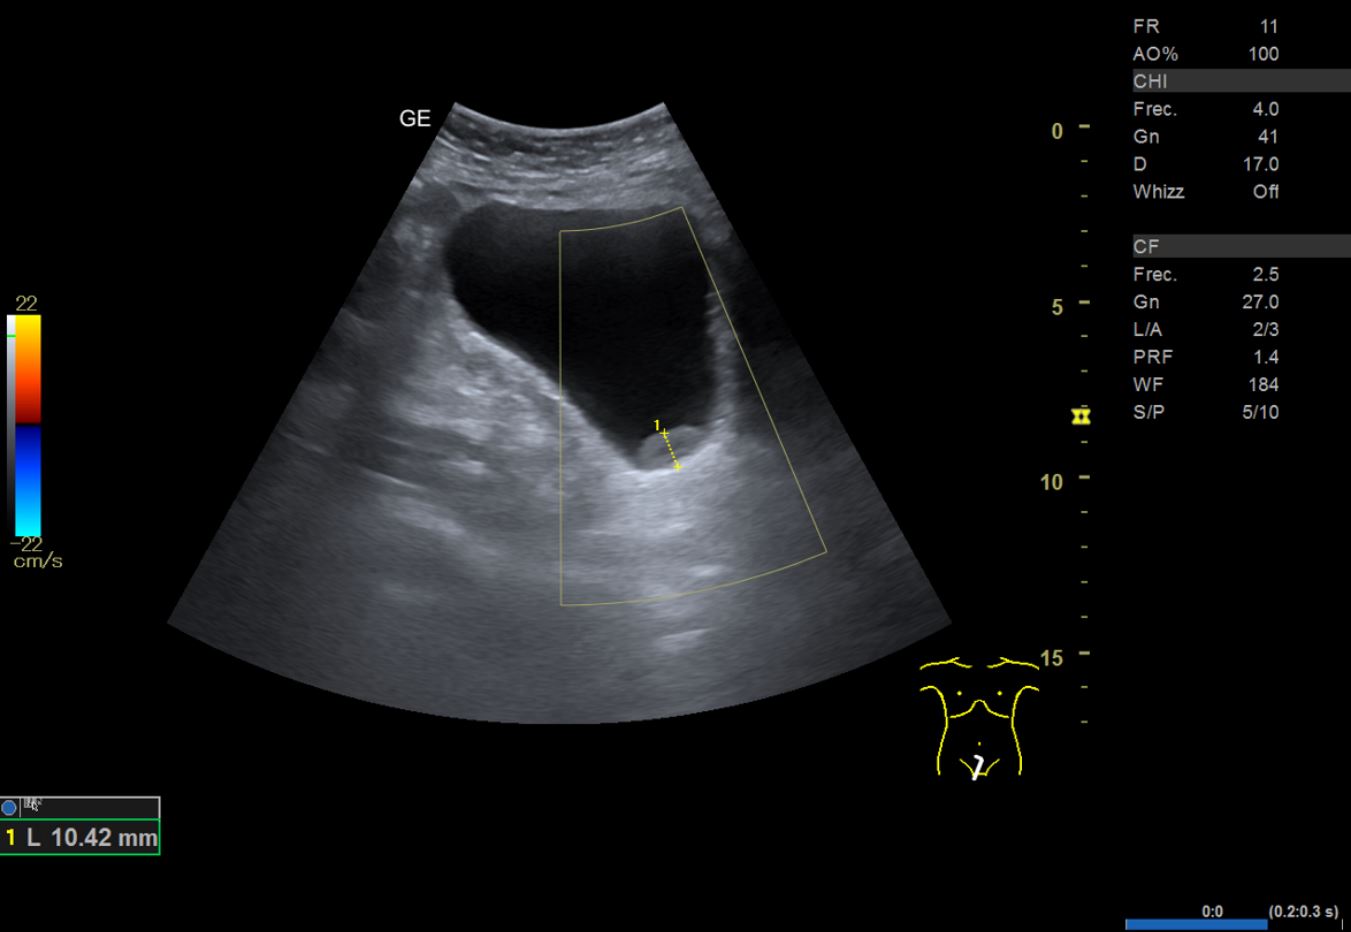

• Ecografía clínica renovesical: riñones con diámetro dentro de la normalidad. Relación cortico-medular normal. Pedículo renal Doppler normal. No se observan litiasis. Vejiga repleta, paredes finas, se observa imagen hipoecogénica en pared posterior lateral derecha que no capta señal Doppler, de unos 2,21 cm de diámetro aproximadamente. Volumen premiccional 290,86 ml, volumen posmiccional 25,54 ml.

En primer lugar se derivó a ginecología por sospecha de sangrado de origen ginecológico donde visualizan ecográficamente un grosor endometrial de 5-6 mm y realizan una biopsia endometrial con resultado de escasos fragmentos superficiales de endometrio atrófico. Tras descartar origen ginecológico y ante la persistencia del sangrado, se orienta como hematuria monosintomática y se realiza una ecografía en el centro de Atención Primaria donde se visualiza imagen hipoecogénica dependiente de la pared vesical.